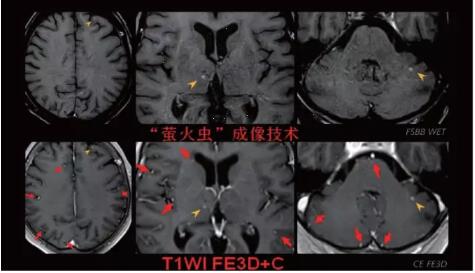

見所未見 微小腫瘤無(wú)處遁藏——

“螢火蟲”成像技術(shù) 顱內(nèi)腫瘤微小病灶檢出新發(fā)現(xiàn)

此技術(shù)主要用于神經(jīng)系統(tǒng)惡性腫瘤,以及其他腫瘤腦轉(zhuǎn)移瘤篩查。傳統(tǒng)情況下做腫瘤腦轉(zhuǎn)移篩查,很容易漏掉5mm以下小病灶,臨床發(fā)現(xiàn)后干預(yù)治療比較晚,要實(shí)現(xiàn)2mm高空間分辨率和超薄層全腦掃描在保證信噪比的情況下需要很長(zhǎng)時(shí)間大概十多分鐘,而且薄層增強(qiáng)序列顱內(nèi)血管呈高亮信號(hào),會(huì)干擾顱內(nèi)小病灶的觀察,血管和小病灶區(qū)分困難。佳能”螢火蟲”成像技術(shù)既可以實(shí)現(xiàn)高空間分辨率和超薄層(最薄可實(shí)現(xiàn)0.2mm)全腦掃描,掃描時(shí)間短,2-3分鐘即可實(shí)現(xiàn)全腦3D掃描,同時(shí)避免了血管高亮信號(hào)的干擾,對(duì)顱內(nèi)原發(fā)或繼發(fā)的微小腫瘤檢查有重大意義。“螢火蟲”成像技術(shù)具有磁敏感效應(yīng),對(duì)于亞急性血敏感敏感,可以區(qū)分出血和強(qiáng)化的腫瘤。